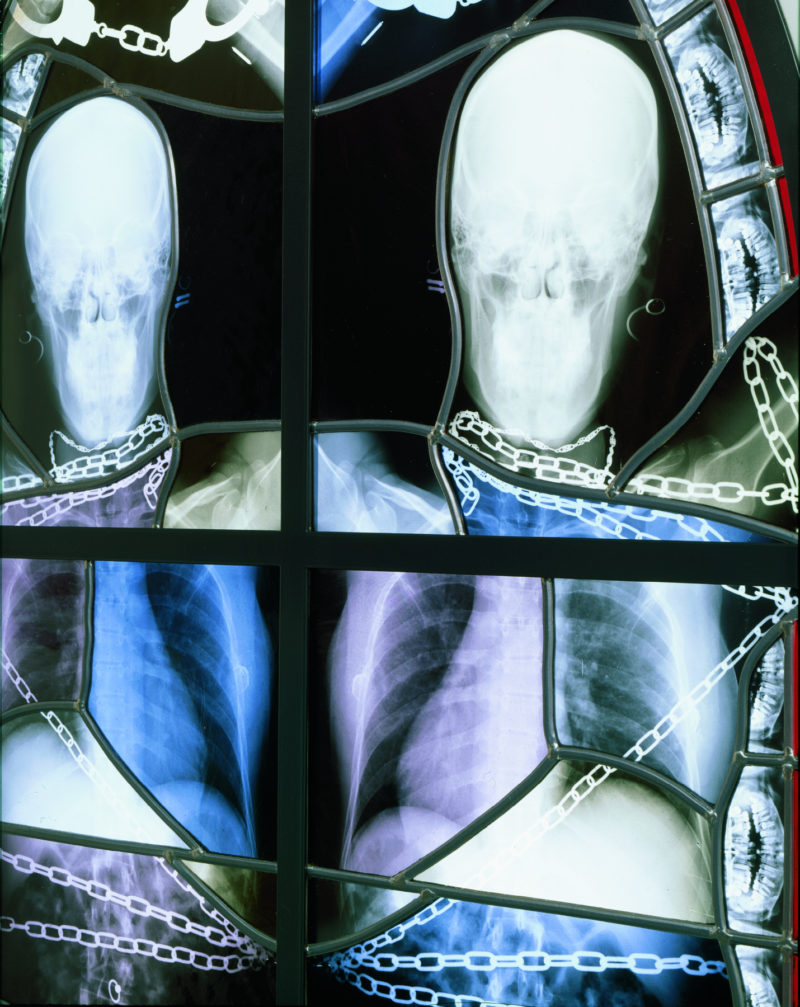

The windows themselves are constructed from authentic medical X‑ray images laminated between panels of glass and assembled within traditional Gothic lead frames. From afar they possess the luminous symmetry of medieval cathedral glass, but the figures revealed in the images are unmistakably skeletal: skulls, bones, and fragments of the human body (and sometimes those of animals) rendered with clinical precision. The sight is simultaneously beautiful and unsettling. These are stained glass windows that could plausibly belong in a church interior, yet their imagery evokes a cold anatomical reality rather than sacred narrative, and that was exactly the intent.

Rather than presenting his x‑ray images as one would if they were simple medical documents, Delvoye now incorporated them into elaborate stained-glass compositions modeled on the window structures of Gothic cathedrals. X‑ray films were mounted between panes of glass and framed with leaded tracery and laser-cut steel structures that echoed the intricate forms of seventeenth-century Flemish Baroque church windows. From a distance the panels resemble traditional ecclesiastical stained glass, glowing with the luminous qualities associated with historic cathedral interiors.

Delvoye initially experimented with embedding the X‑ray film between layers of glass. Later he refined the process in order to integrate the imagery more completely into the architecture of the windows. “In the beginning, I asked a stained glass window maker to do double glass, and in between the glass we did the x‑ray. Which is in itself transparent,” he explains, “Then, I thought if I really wanted to integrate them into something a bit architectural – because I got a bit more ambitious afterwards – then I have to put the x‑ray image on the glass itself. It’s a pigment we burn into the glass, and that pigment I apply with silk screen. They’re very beautiful because the pigment is a very interesting material, it’s a medieval material.”

The windows were organized into several thematic groups. Some panels represented classical muses, others referenced the months of the year, while a third group was designed specifically for architectural installations inside chapel-like structures fabricated from laser-cut steel. These chapels ranged from smaller architectural models to full-scale structures resembling miniature cathedrals.

A key example of this approach appeared in the form of the work Chapelle from 2006. These installations were designed to be viewed inside of a fully realized architectural space, intensifying the spiritual dimension of the works. Visitors step into an enclosed space, built to resemble a chapel, containing the glowing radiographic panels, a viewing experience that mirrors the hidden, observational nature of medical imaging itself. By integrating colored glass with the radiographic material, Delvoye preserved the transparency of the X‑rays while recreating the atmospheric light effects associated with historical stained glass.

Inside the chapels the luminous panels produce a striking visual effect. Radiographic images of hips, skulls, ribs, and spines intertwine to form compositions that glow like traditional stained glass. Because X‑rays transmit light in much the same way as colored glass, the panels illuminate easily, producing a glittering yet macabre atmosphere. The resulting environment is both beautiful and unsettling.